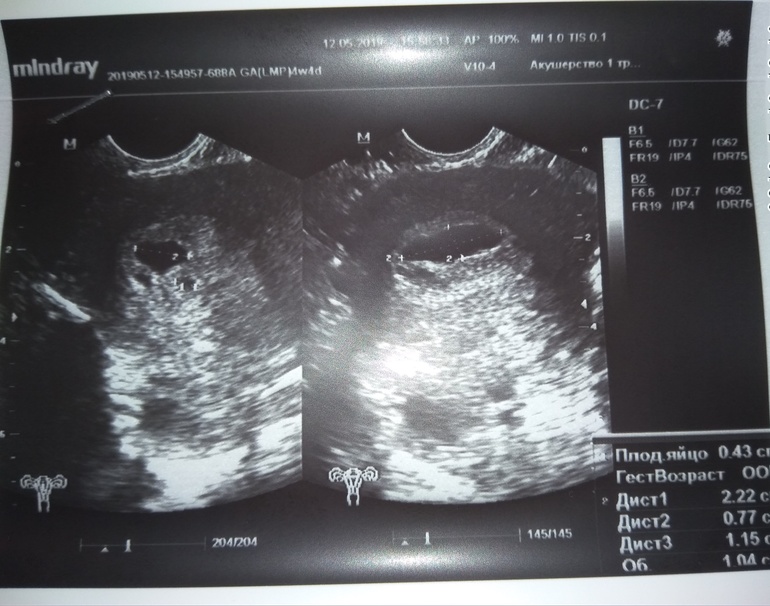

Вот, девочки, кто разбирается в узи. Сначала думал, что большое пятно это ПЯ без эмбриона, но написал все таки, что ПЯ 4 мм, а это гематома

Сначала гематому принял за пустое плодное яйцо, сказал анэмбриония. Я сказала, что срок у меня точно меньше. Тогда нашел маленькое ПЯ, а это сказал гематома. Но раз такая огромная, то замрет по любому

Я от шока не так в посте написала. Он имел ввиду, что не уже замершая, а то что будет по любому или выкидыш со дня на день... А щас плодное яйцо размером по сроку. Правда он сначала сомневался что из этого ПЯ, потом написал все таки, что яйцо 4 мм и большая гематома